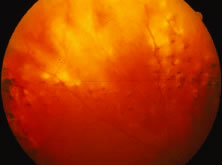

The ARN patient typically presents with progressive visual blurring in one or both eyes occurring over several weeks. These patients often are initially treated with corticosteroids, antitoxoplasmosis drugs, and other medications before arriving at the correct diagnosis. Examination reveals a prominent anterior uveitis that may be granulomatous or nongranulomatous (Fig. 1). Inflammatory signs may be prominent and cause severe pain (Fig. 2). The uveitis may be diffuse and so severe that it causes proptosis. These signs, and the diffuse vitreitis that makes the view of the retina difficult, may contribute to the high degree of delayed and/or misdiagnosis that occurs in the early stages of the disease. Significant vitreous cellular infiltration is seen in the presence of retinitis that is manifest by opacification of the retina, often most prominently in the periphery. Posterior pole involvement may include retinitis, as well as inflammation of the optic nerve head. Optic neuropathy might be the first sign of ARN with subsequent development of other retinal manifestations.8 Ultrasonography and computed tomography (CT) might be helpful in cases of ARN associated with optic nerve edema revealing enlargement of the optic nerve sheath.9 Even in ARN patients who are not immunocompromised and who have no clinical evidence of encephalitis, magnetic resonance imaging of selected cases has shown lesions of the lateral geniculate, optic tracts, and chiasma, which suggests that the virus spreads through the central nervous system (CNS) by axoplasmic transport from the retinal ganglion cells.10 A secondary retinal vasculitis is common, often accompanied by a mild number of retinal hemorrhages. Days to weeks after onset of the infection, the discrete peripheral lesions typically coalesce into a white or yellow ring of infected retina, and the associated vasculature is obliterated (Fig. 3). Necrotic retina desquamates into the vitreous resulting in vitreous sheets.3,6 Eventually, most untreated eyes can be expected to develop retinal detachment resulting from development of multiple full-thickness retinal breaks accompanied by traction or exudation.11 Giant retinal pigment epithelial tears have also been reported.12